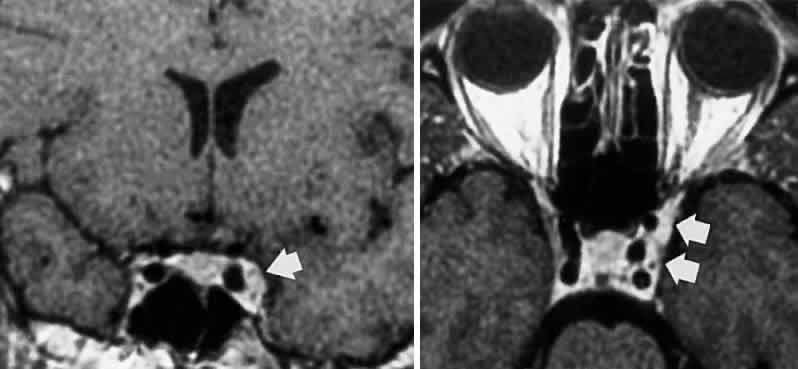

Acquired bi-nuclear total ophthalmoplegia is occasionally seen (Fig. 11), as reported by Masucci.82 These findings are the result of thrombotic or embolic processes at the level of the basilar bifurcation, with occlusion of the median mesencephalic perforating arteries. Congenital bilateral total ophthalmoplegia with or without levator and pupil sparing has been reported and may be associated with dysplasia of the corpus callosum.83

Fig. 11. Bilateral oculomotor palsies (nuclear?) associated with abrupt onset of vertigo and mild left hemiparesis.